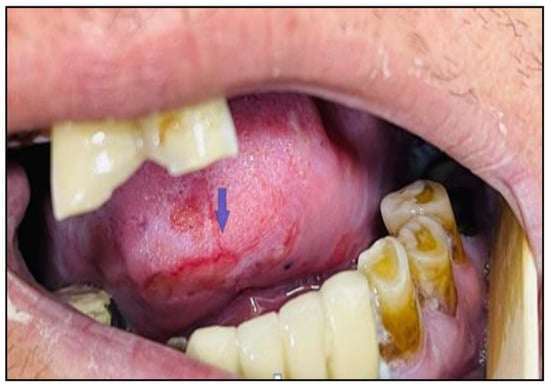

3.8. Osteoradionecrosis (ORN)

Osteoradionecrosis (ORN) refers to ischemic bone necrosis that is not healing due to RT exposure (Figure 7). It is characterised by soft tissue necrosis and may last three months [7,42]. The history of ORN goes back 100 years to when it was first noted in 1922 by Regaud. ORN is uncommon (5–15% only) but can have a significant negative influence on QoL [65,66]. Modern RT techniques can lower the ORN risk of occurrence. In this review, ORN prevalence was 7.4% with conventional RT, 6.8% with chemoradiation, 5.3% with brachytherapy, and 5.1% with IMRT [9]. A newer study showed the lowest incidence of ORN with proton RT compared to IMRT, 2% vs. 7.7%, respectively [67]. In addition to the selective suppression of osteoclasts in radiated bone, the pathophysiology of ORN is attributed to the concept of “three-H-H-H” (hypocellularity, hypervascularity, hypoxia) of bone that is caused by RT [68]. Subsequent trauma (primarily dental extraction) or spontaneous disruption of the oral mucosa will then be associated with a significant amount of bone fibrosis and damage to the remodeling system (osteocytes, osteoblasts, and osteoclasts) [69]. These alterations eventually result in a non-healing process that can lead to necrosis with or without infection [8,11,68].

Figure 7.

After receiving radiation therapy, a male patient with HNC developed osteoradionecrosis, which is defined as bone necrosis combined with soft tissue necrosis (A) and osteoradionecrosis on an X-ray (B).